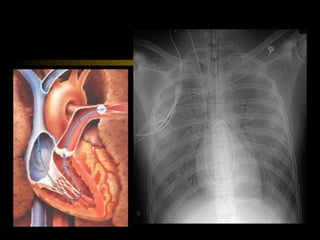

•   Rx de tórax AP simples

Choque • MONITORIZAÇÃO • Oximetria • Gasometria Arterial • Bioquímicos: U, C, Na, K • Rx de tórax AP simples • HEMODINÂMICA